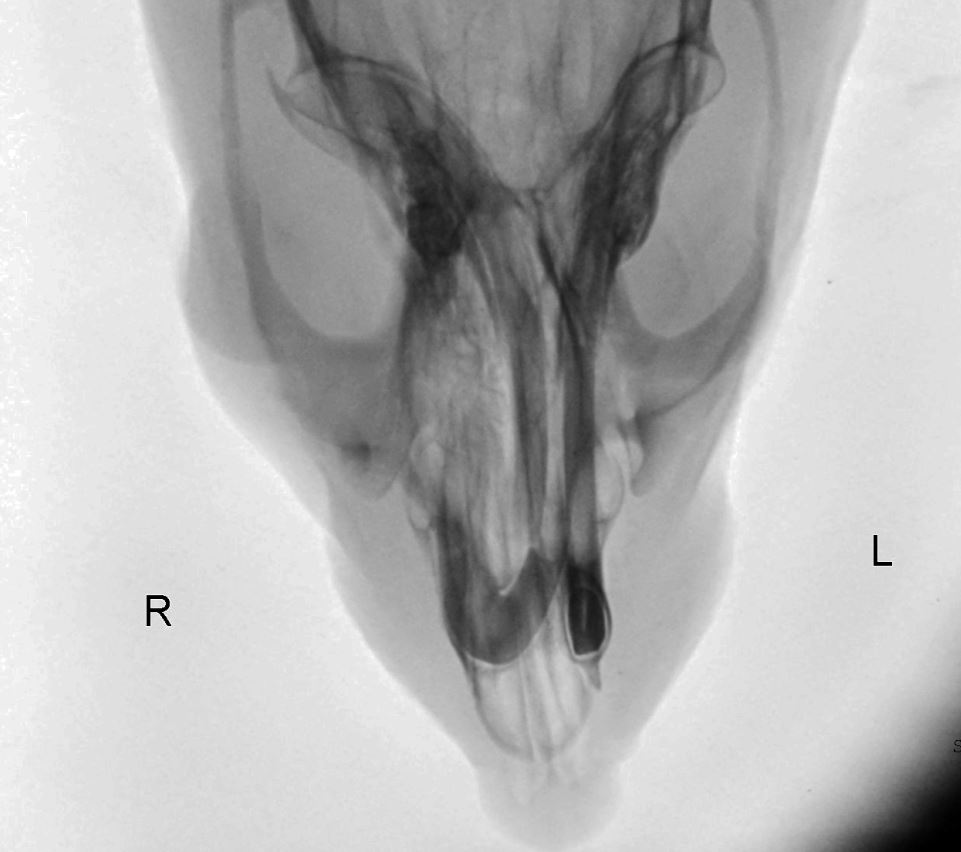

Röntgenbilder: links 14.1. und rechts am Tag der Einschläferung 12.2.

Die Erkrankungsursache der

untersuchten euthanasierten Ratte bestand in einem periorbital

lokalisiertem infiltrativ wachsenden Plattenepithelkarzinom,

einer fibrinös-eitrigen anterioren Uveitis mit assoziierter

erosiv-eitriger Keratitis und einer eitrig-nekrotisierenden

Lymphadentitis.

Plattenepithelkarzinome sind bösartige, epitheliale Tumore, welche

vom Plattenepithel der Haut oder Schleimhaut ausgehen. Sie können

unter Anderem

aus den Bereichen der Konjunktiva, Limbus, Augenlid oder Nickhaut

hervorgehen. Der Tumor zeigt ein lokal invasives Wachstum und kann

unterschiedlich

ausdifferenzierte Epithelanteile aufweisen. Zu den

prädisponierenden Faktoren zählt eine Belastung mit

UV-Strahlung, eine helle Fellfarbe oder geringe

Pigmentierung der Kopfregion. Die darüber hinaus vorliegenden

eitrig-dominierten Entzündungen des Auges sowie des Lymphknotens

sprechen für eine

primäre oder sekundäre bakterielle Beteiligung, welche im

Kontext lokaler mechanischer oder physikalischer Reize mit einem

Erregereintrag einhergehen können.